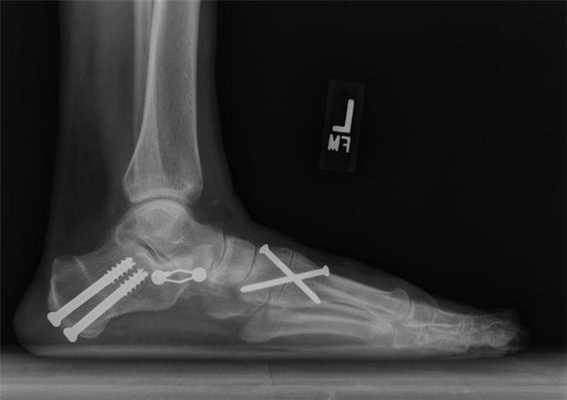

Артродезирование голеностопного сустава выполнялось с использованием в качестве фиксатора винтов. Применялись латеральный и медиальный доступы посредством внутренних и наружных транснадлодыжечных артротомий с резекцией хрящевых поверхностей лодыжек. Затем осуществлялась корригирующая остеотомия как большеберцовой, так и таранной костей с удалением суставного хряща и субхондрального слоя. Стопа устанавливалась в физиологически выгодное положение и фиксировалась двумя взаимно перекрещивающимися канюлированными винтами, введенными по направляющим спицам через большеберцовую кость в таранную. Латеральную лодыжку фиксировали одним или двумя винтами к большеберцовой кости, стабилизируя зону артродеза.

При рентгенологическом обследовании пациентов за период наблюдения у всех сформировался костный анкилоз голеностопного сустава. Прогрессирование остеоартроза подтаранного сустава, который клинически проявлялся умеренным болевым синдромом и наличием хромоты, отмечено только у одного пациента во 2 группе больных. При анкетировании его по шкале AOFAS результат составил 48 баллов. Учитывая наличие остеоартроза подтаранного сустава III стадии, положительный эффект от диагностической блокады с раствором новокаина, пациенту был выполнен артродез таранно-пяточного сустава винтами. На контрольном осмотре через 1 год после операции диагностирован костный анкилоз. Пациент не предъявляет жалоб на боли, передвигается без дополнительных средств опоры даже на длительные расстояния, AOFAS - 78 баллов.